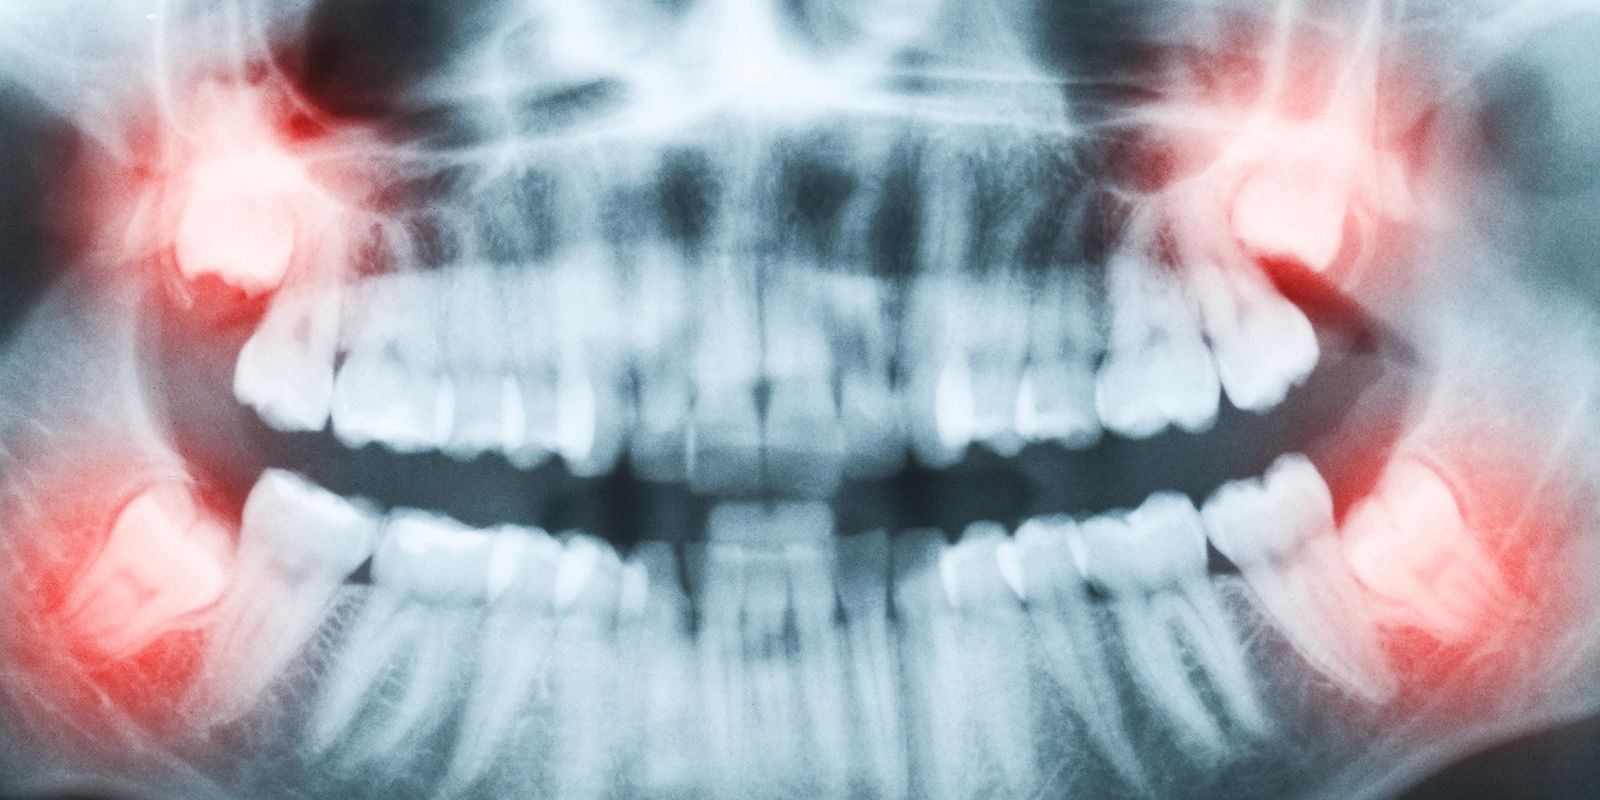

抜歯の前には、CTやデジタルレントゲンを使用して、親知らずの根の形状や周囲の神経・血管との位置関係を正確に把握します。精密な検査に基づいて治療計画を立て、できる限り痛みや腫れを抑えた抜歯を行います。

抜歯の前に、デジタルレントゲンやCTで親知らずの状態を詳しく確認します。特に下顎の親知らずは、顎の中を通る神経(下歯槽神経)に近い位置にあることが多いため、神経との距離を正確に把握することが重要です。検査結果をもとに、安全で確実な抜歯方法を計画します。